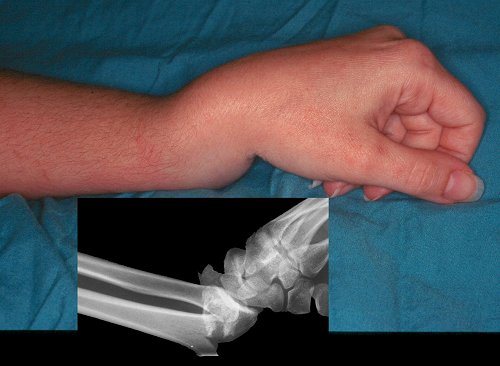

Figure Legend: Acute deformity.  The angulation of this fracture is obvious even in an unconscious patient.  Above, the fracture; below, the x-ray.